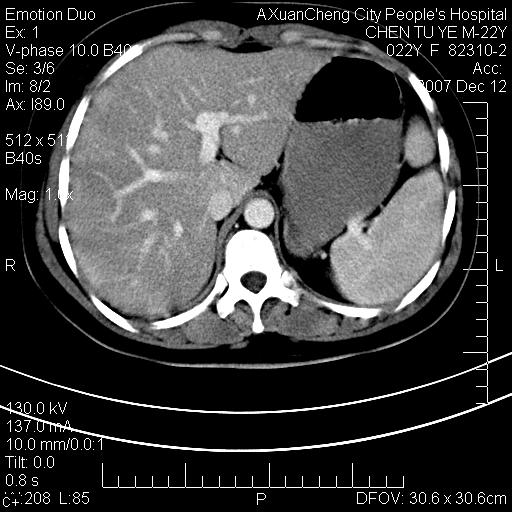

超声提示肝右前叶占位,约2.5cm.

各位战友看看病灶在什么地方,可是右前叶进肝裂部低密度影,平扫ct值约10以下,增强后增高明显

肝圆韧带

1 脾大,慢性肝损伤. 2 肝脏脂肪侵润.  3 你所指的部位疑点,我没看出有问题.

脂肪肝.楼主所指部位不考虑异常,为肝圆韧带影.

不均匀脂肪浸润,版主所说的病灶为肝园韧带服着点。

考虑肝圆韧带。